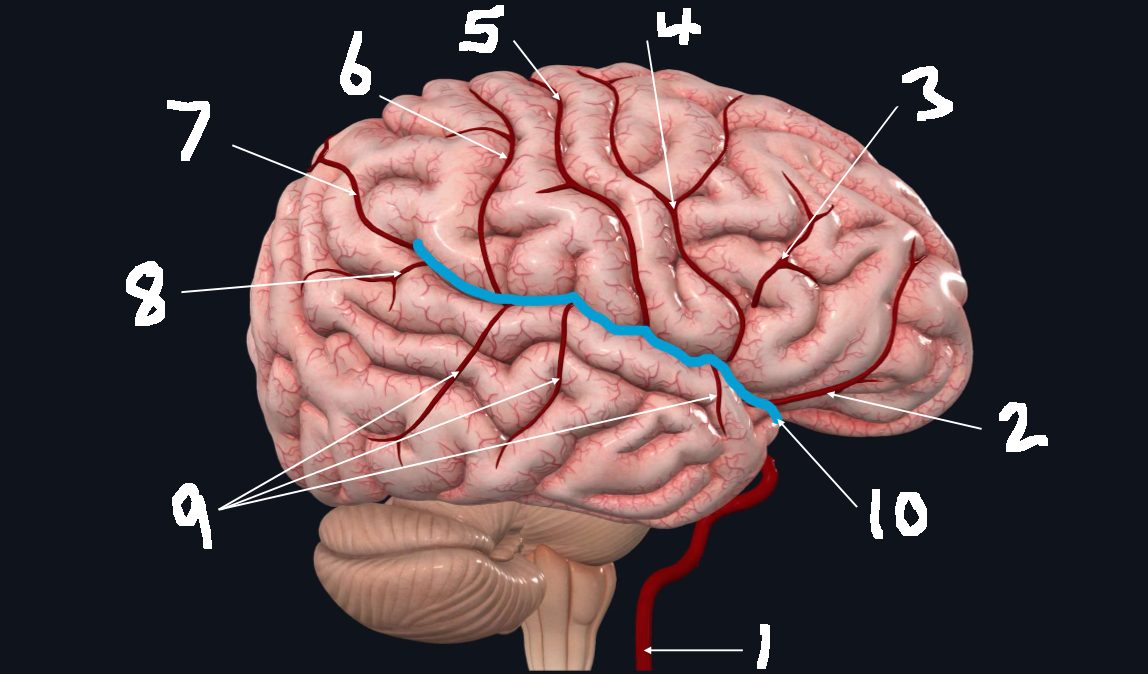

What is 1?

internal carotid artery

What is 2?

orbitofrontal artery

What is 3?

prefrontal artery

What is 4?

precentral artery

What is 5?

central artery

What is 6?

postcentral artery

What is 7?

posterior parietal artery

What is 8?

angular artery

What is 9?

temporal arteries (anterior, middle, posterior)

What is 10?

lateral cerebral fissure